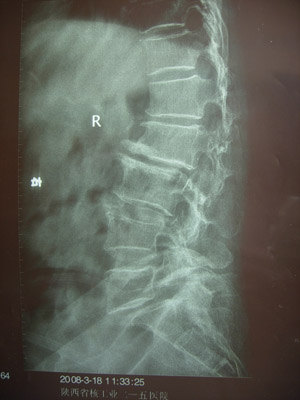

病例一

术前X线片